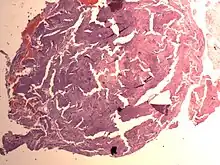

Endometrial Stromal Nodule

An endometrial stromal nodule is a noncancerous tumor of the uterus.[2]

It is a subtype of endometrial stromal tumor belonging to the mesenchymal tumors of the main body of the uterus.[1] The appearance of the cells is identical to normal endometrial stromal cells.[1] This can only be differentiated from low-grade endometrial stromal sarcoma by confirming lack of infiltration.

The differential includes cellular leiomyoma. Diagnosis may be aided by immunostaining; endometrial stromal nodules are positive for CD10; leiomyomas are positive for caldesmon and desmin (and sometimes CD10).